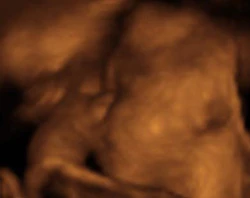

El Obispo de Angers (Francia), Mons. Emmanuel Delmas, proclamó el milagro número 68 oficialmente reconocido de la curación de un... Leer más